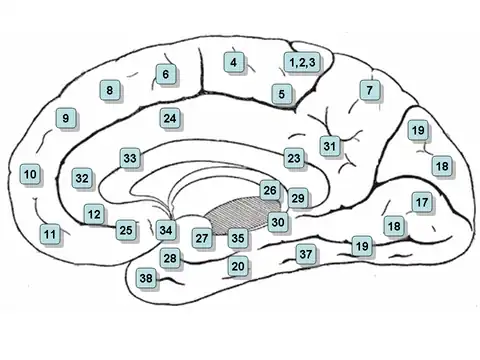

Medial surface of the brain with Brodmann's areas numbered. | |

Brodmann area 34 is a part of the brain.

It has been described as part of the entorhinal area[1] and the superior temporal gyrus.[2]

The entorhinal area is the main interface between the hippocampus and neocortex and involved in memory, navigation and the perception of time.[3] Destruction of Brodmann area 34 results in ipsilateral anosmia.